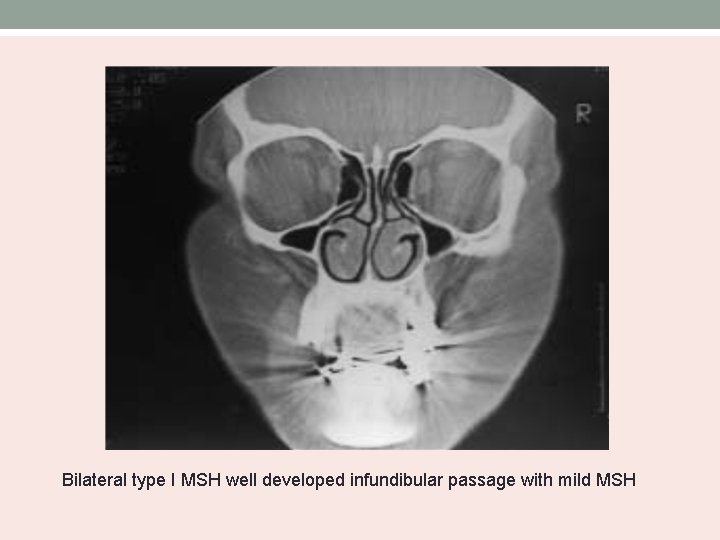

Bolger’s MSH Classification • Based on the degree of pneumatization and lateral nasal wall abnormalities. Type Uncinate process MSH I normal mild II Absent severe III Absent Cleft-like

Bilateral type I MSH well developed infundibular passage with mild MSH